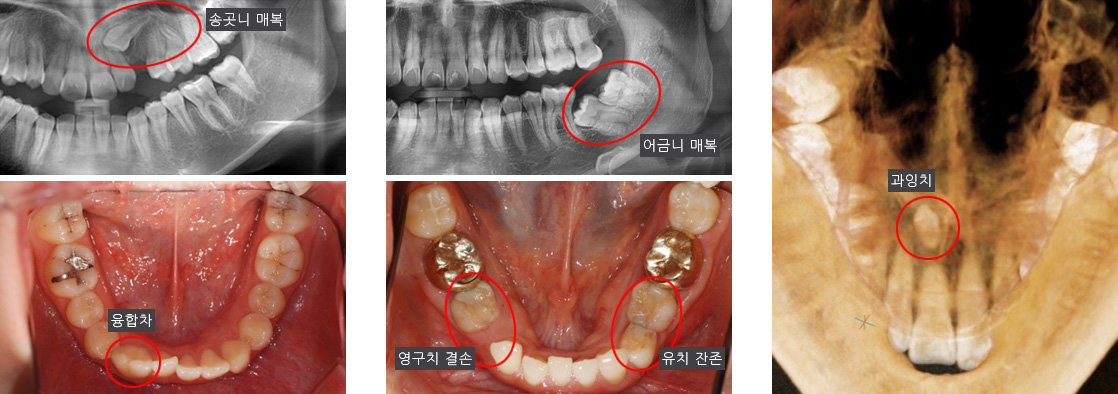

과거에 비해 현대인들에게서 부정교합의 비율이 증가한 것은 진화적 측면에서 그 원인을 찾을 수 있습니다.

가공되지 않아 질기고 딱딱한 음식을 섭취하던 과거와 달리 현대인의 식습관이 변화했으며, 그로 인해 질긴 음식을 주로 담당하던

치아가 퇴화하고 아래턱 크기가 감소하는 등의 변화가 나타났습니다. 이 결과로 매복치, 기형치, 과잉치, 맹출 장애 등

다양한 형태로 치아 맹출 이상이 나타납니다.